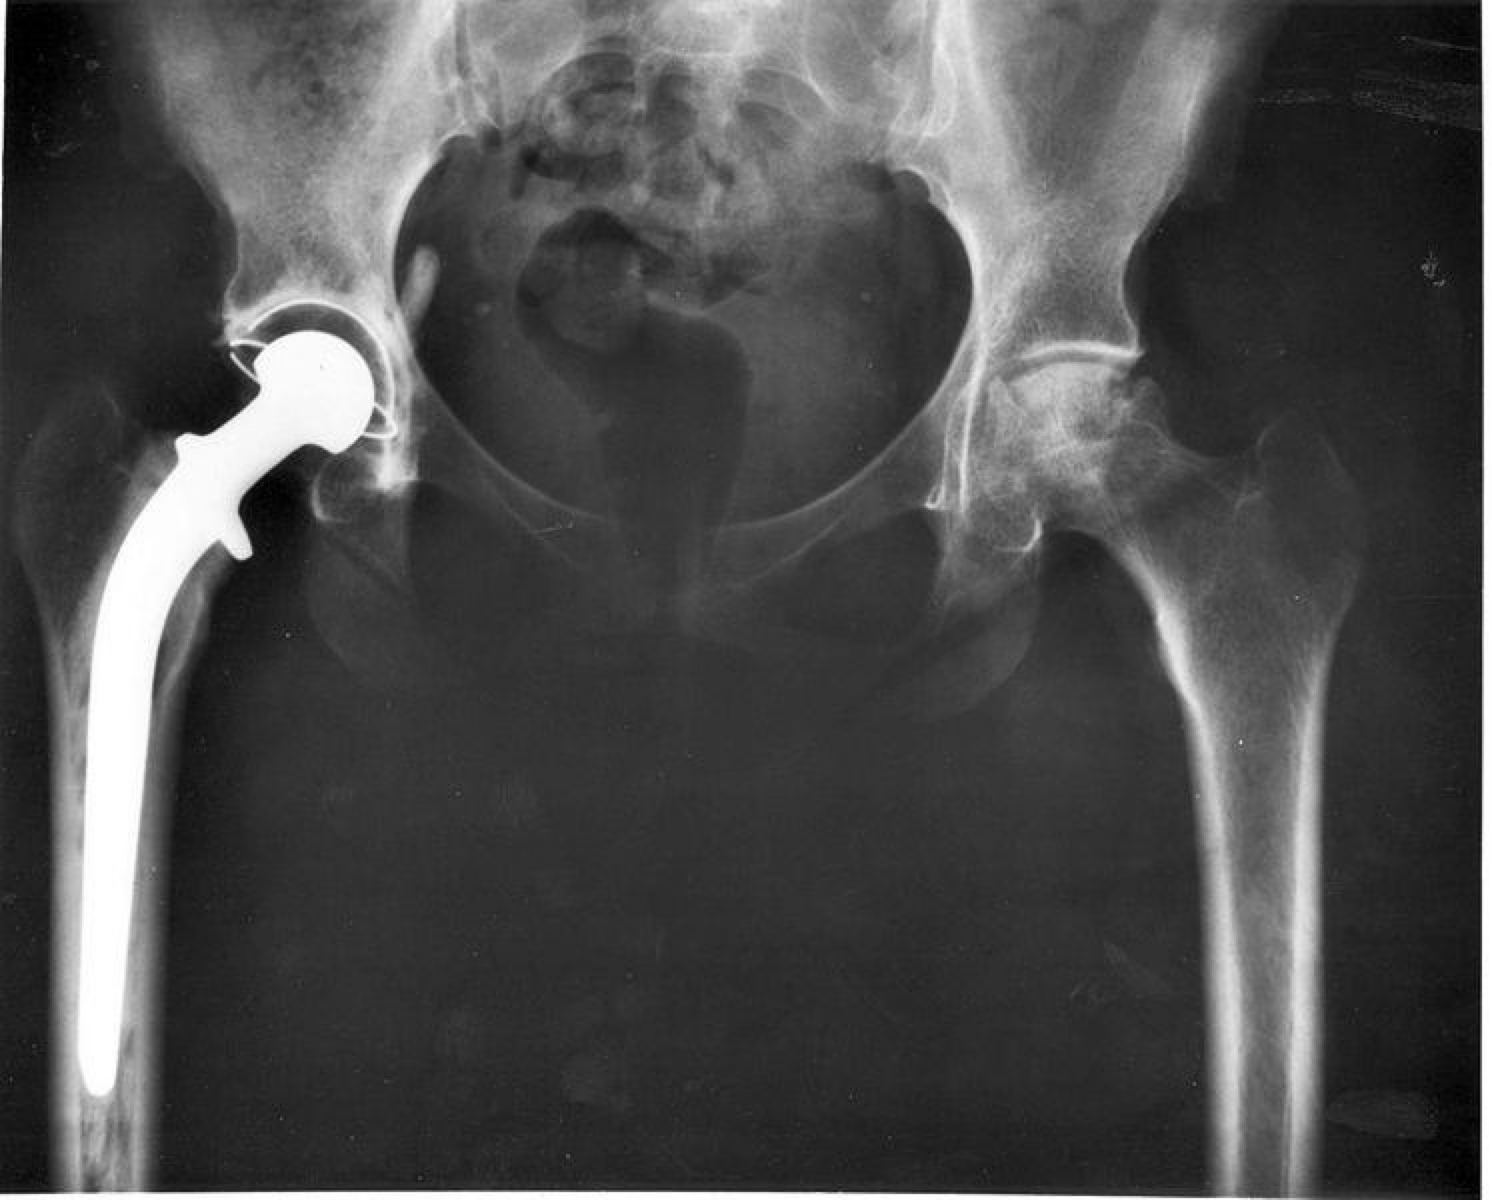

Primary THA

Implant Fixation & Bearing Surface

• Most common construct: Cemented MoP, 4.87% revision in 14 years

• 75 years: All bearing surface combinations (except MoM) perform similarly

• <55 years: CoP shows better results (<4%) compared to MoP (8-10%)

THA of Choice

• Cemented Exeter Hip: Long-term performance, ODEP rating A* at 10 years

• Ceramic Femoral Head with 1st or 2nd gen XLPE

• <55 years: Discuss uncemented THA option

Why Not Uncemented?

• Dorr C femur

• Elderly

• Pathological bone

• Stress shielding, thigh pain

• Difficult to revise

Uncemented THA Principle

Dynamic biological fixation with lifelong bond between bone and implant.

Methods:

- Bone ingrowth (porous coating)

- Bone ongrowth (grit-blasted/plasma-sprayed surface)